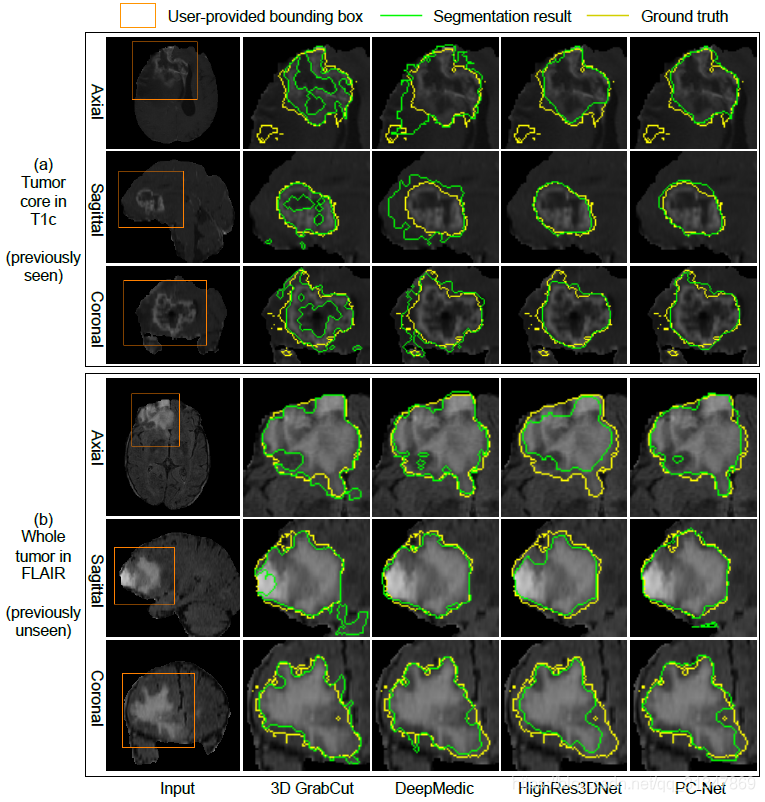

2. 3D 图像分割

数据集:2015 Brain Tumor Segmentation Challenge (BRATS) training set

(1)PC-Net 实现的初始分割结果与其他方法的对比:

(a)图:3D GrabCut 和 DeepMedic 效果都不好,前者比 ground truth 小,后者比 ground truth 大。HighRes3DNet 虽然和 PC-Net 效果差不多,但是 PC-Net 计算消耗存储空间小。

(b)图,对于未见图像的分割,由于肿瘤区域强度的不一致,3D GrabCut分割效果不好。

从下表看出,DeepMedic 在 T1c 上的准确率比较低,在 FLAIR 上的准确率较高,HighRes3DNet 刚好和它相反。

原因:DeepMedic 的感受野比较小,比较依赖局部特征,T1c 的图像比较复杂,所以处理效果不好。